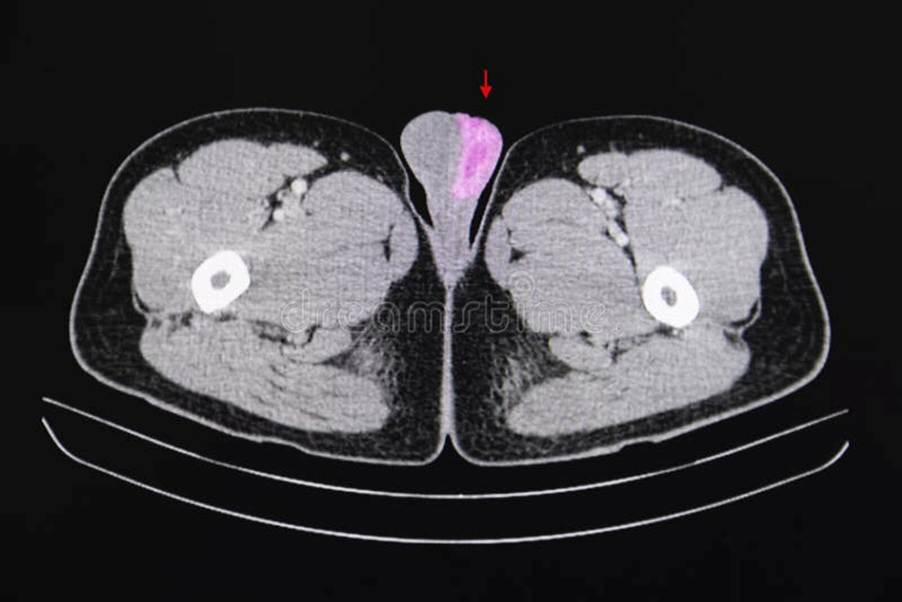

Computed Tomography

Some researchers in the field consider CT rarely needed and advise avoiding it due to ionizing radiation. However, other researchers consider that cross-sectional imaging of the abdominopelvic region is needed for all germ cell tumours in the following situations:

To identify retroperitoneal lymph node disease arising from the primary testis cancer.

Patients with high levels of AFP, β-hCG, and LDH should undergo CT of the chest, abdomen, and pelvis for staging (Stephenson et al., 2019).

If normal levels, it is rare for metastasis outside the retroperitoneal lymph node.

CT scan of the brain in cases of choriocarcinoma and high levels of β-hCG, as researchers have shown the tumour to go through hematogenous routes.

CT scan of the testicular region and surrounding tissue (Dreamtimes, 2025)